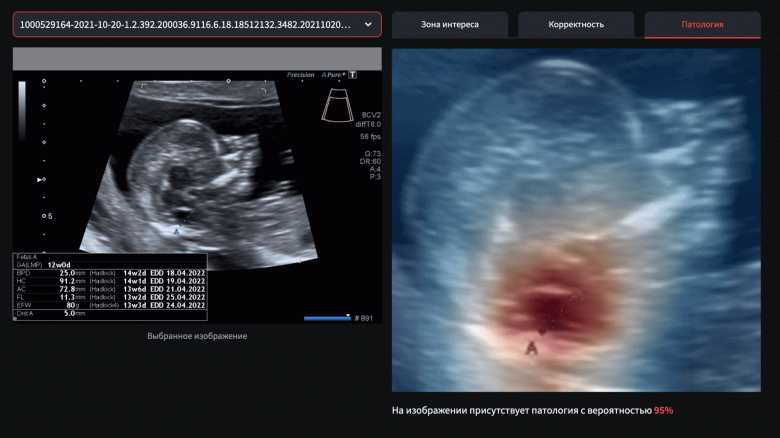

Медицинский специалист может загрузить результаты УЗИ, сделанные во время первого скрининга. Решение автоматически проанализирует снимок и поможет врачу определить вероятность, с которой на изображении присутствуют признаки spina bifida. Если есть вероятность наличия патологии, врач сможет направить пациентку на дополнительное обследование в крупные перинатальные центры России, чтобы назначить дальнейшее лечение.